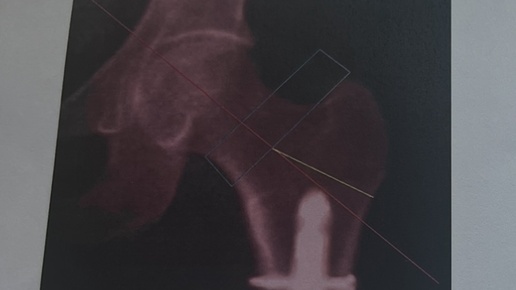

С какими только протоколами денситометрии не обращались ко мне на прием! А ведь ориентируясь на это исследования мы порой принимаем важные решения о лечении. Денситометрия – это метод диагностики плотности костной ткани. Проведение двухэнергетической рентгеноденситометрии (DXA) поясничного отдела позвоночника и проксимального отдела бедренной кости рекомендовано для диагностики и оценки эффективности проводимой терапии остеопороза. Протокол обычно выглядит так: В идеальной ситуации мне приносят...

Для оценки состояния костей проводятся разные исследования. В каких случаях необходима именно денситометрия? Рассказывает врач-рентгенолог высшей квалификационной категории, заведующий рентгеновским отделением Городской клинической больницы № 52 Василий Паршин. – В чем преимущество денситометрии перед другими инструментальными исследованиями костей: рентгена, МРТ? – Денситометрия используется для анализа минеральной плотности костной ткани и позволяет выявить остеопороз и предшествующую ему остеопению...

Денситометрия — это диагностическая процедура, предназначенная для измерения плотности костной ткани. Этот метод особенно важен для оценки риска остеопороза и других заболеваний, связанных с потерей костной массы. Денситометрия помогает врачам выявить изменения в костной ткани на ранних стадиях, что позволяет своевременно начать лечение и предотвратить серьезные осложнения. Принципы работы денситометрии Денситометрия основывается на использовании различных методов визуализации, таких как рентгенография или ультразвук, для измерения плотности костной ткани...